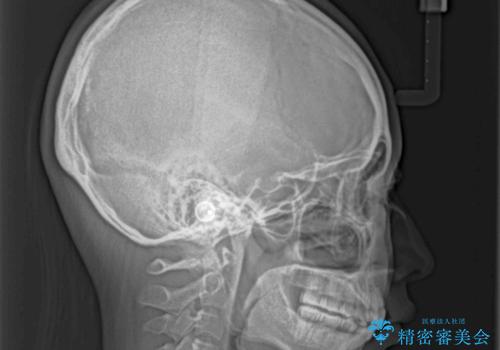

- 下唇に跡がつくほどに飛び出した上顎前歯を気にして来院された患者様です。

来院された時から4本の抜歯が必要であることを理解されていらしており、通法通り上下左右の第一小臼歯4本を抜歯し、ワイヤー装置にて矯正治療を行うこととしました。

順調に治療が進み、2年弱で想定していたとおりの仕上がりにて治療を終えることができました。